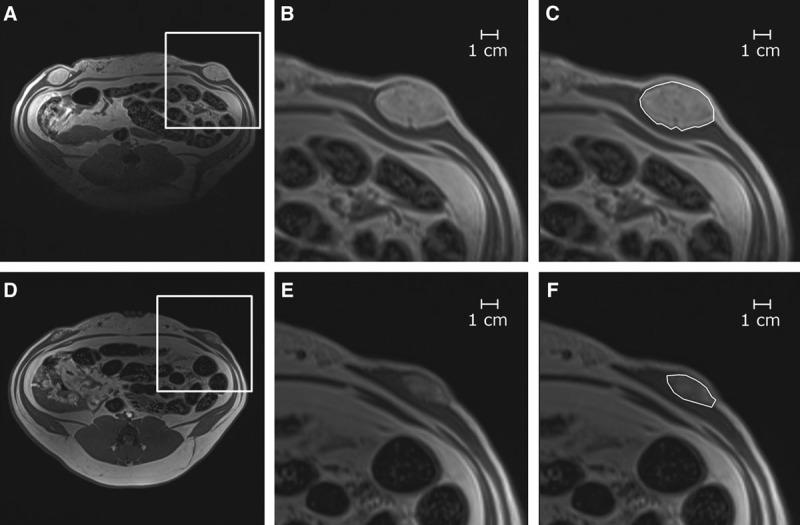

METHODS

Fat grafting was performed as bolus injections and structural fat grafting. Graft retention was assessed by magnetic resonance imaging after 120 days. The stromal vascular fraction (SVF) was isolated from excised fat and liposuctioned fat from different anatomical sites and analyzed. Porcine adipose-derived stem/stromal cells (ASCs) were cultured in different growth supplements, and population doubling time, maximum cell yield, expression of surface markers, and differentiation potential were investigated.

RESULTS

Structural fat grafting in the breast and subcutaneous bolus grafting in the abdomen revealed average graft retention of 53.55% and 15.28%, respectively, which are similar to human reports. Liposuction yielded fewer SVF cells than fat excision, and abdominal fat had the most SVF cells/g fat with SVF yields similar to humans. Additionally, we demonstrated that porcine ASCs can be readily isolated and expanded in culture in allogeneic porcine platelet lysate and fetal bovine serum and that the use of 10% porcine platelet lysate or 20% fetal bovine serum resulted in population doubling time, maximum cell yield, surface marker profile, and trilineage differentiation that were comparable with humans.

脂肪移植采用团注注射和结构性脂肪移植。120天后通过磁共振成像评估移植保留情况。从不同解剖部位切除的脂肪和吸脂脂肪中分离出基质血管成分(SVF)并进行分析。将猪脂肪来源的干细胞(ASC)在不同生长补充剂中培养,并研究群体倍增时间、最大细胞产量、表面标志物表达和分化潜能。

结果

乳房的结构性脂肪移植和腹部的皮下团注移植分别显示平均移植保留率为53.55%和15.28%,这与人类报告相似。吸脂获得的SVF细胞比脂肪切除少,腹部脂肪的SVF细胞/克脂肪最多,SVF产量与人类相似。此外,我们证明猪ASC可以很容易地在同种异体猪血小板裂解物和胎牛血清中分离并在培养中扩增,并且使用10%猪血小板裂解物或20%胎牛血清导致的群体倍增时间、最大细胞产量、表面标志物谱和三系分化与人类相当。